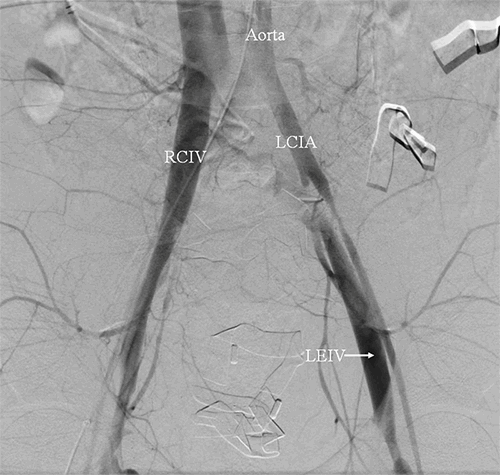

Once in the interventional radiology suite, an arteriogram revealed large bilateral AVFs between the common femoral arteries and veins (Figure 1 and Figure 2).

Figure 1. Aortic run of angiogram with injection of contrast into femoral arteries with immediate opacification of the venous system bilaterally, suggesting presence of an arteriovenous fistula. LCIA=left common iliac artery; RCIV=right common iliac vein; LEIV=left external iliac vein.